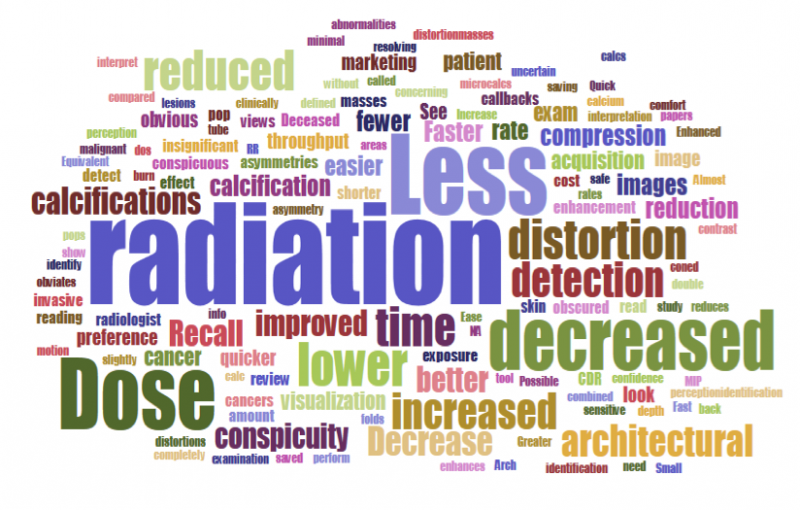

Despite decades of progress in breast imaging, one challenge continues to test even the most skilled radiologists ...

Many mammography practices that use digital breast tomosynthesis (DBT) continue to use dosed digital mammography to ...